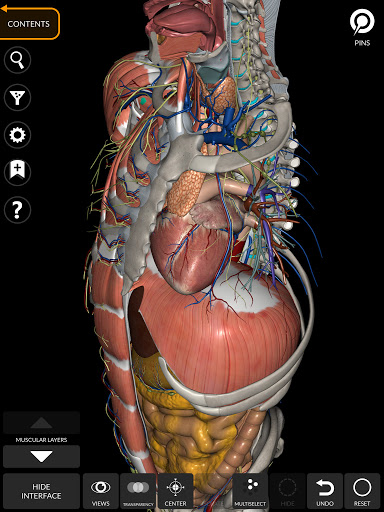

"Anatomy 3D Atlas" cho phép bạn nghiên cứu giải phẫu người theo cách dễ dàng và tương tác.

Thông qua giao diện đơn giản và trực quan, bạn có thể quan sát mọi cấu trúc giải phẫu từ mọi góc độ.

Các mô hình giải phẫu 3D đặc biệt chi tiết và có kết cấu lên đến độ phân giải 4k.

Việc phân chia theo vùng và chế độ xem được xác định trước giúp quan sát và nghiên cứu các bộ phận hoặc nhóm hệ thống riêng lẻ và mối quan hệ giữa các cơ quan khác nhau.

MÔ HÌNH GIẢI PHẪU 3D

• Hệ thống cơ xương

• Hệ thống tim mạch

• Hệ thống thần kinh

• Hệ thống hô hấp

• Hệ thống tiêu hóa • Hệ thống tiết niệu sinh